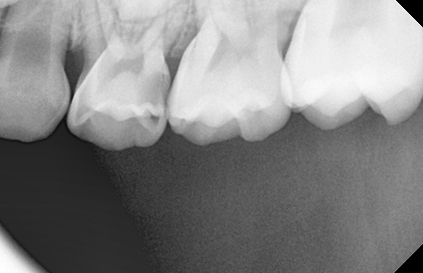

유치는 영구치보다 충치의 발생빈도 및 진행속도가 빠릅니다.

특히 치아 사이면이 쉽게 썩는데, 잘 보이지 않아 가정에서 충치를 발견했을 때에는 이미 치료시기를 놓친 경우가 많습니다.

한편, 유치 치수(치아신경)는 상대적으로 커 조금만 깊이 충치가 진행되면 신경치료까지 해야 하는 경우가 많습니다.